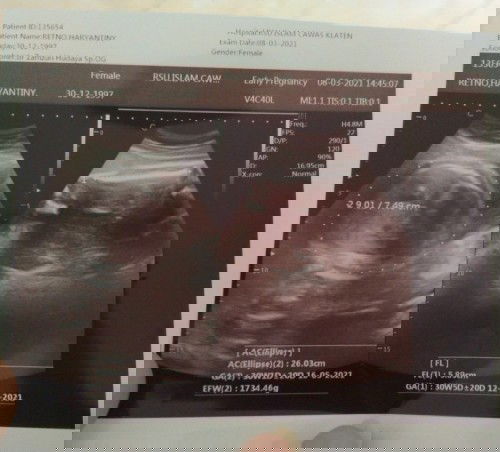

Masuk 40week 2hari....si dede masih betah😌 Katanya klo menjelang persalinan, pasti sakit pinggang,sakit di Miss v,dll,,,,... Saya hanya merasakan perut lbh sering kencang, kaki mulai bengkak 1 Minggu terakhir.....wajar gac sih Bun? Selebihnya masih bisa aktivitas normal(kecuali angkat² cucian😆) ....... Udach kelewat hpl😌 dikasih waktu sama dokter seminggu~...... Kdng sempet kepikiran , pengen bgt si dede launcing 😌 #bantusharing #ingintahu #firstbaby #1stimemom